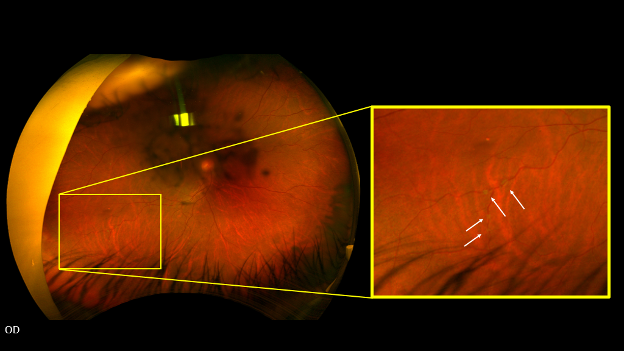

Detailed fundus photography of the right eye depicts white deposits (white arrows) along the peripheral vasculature.